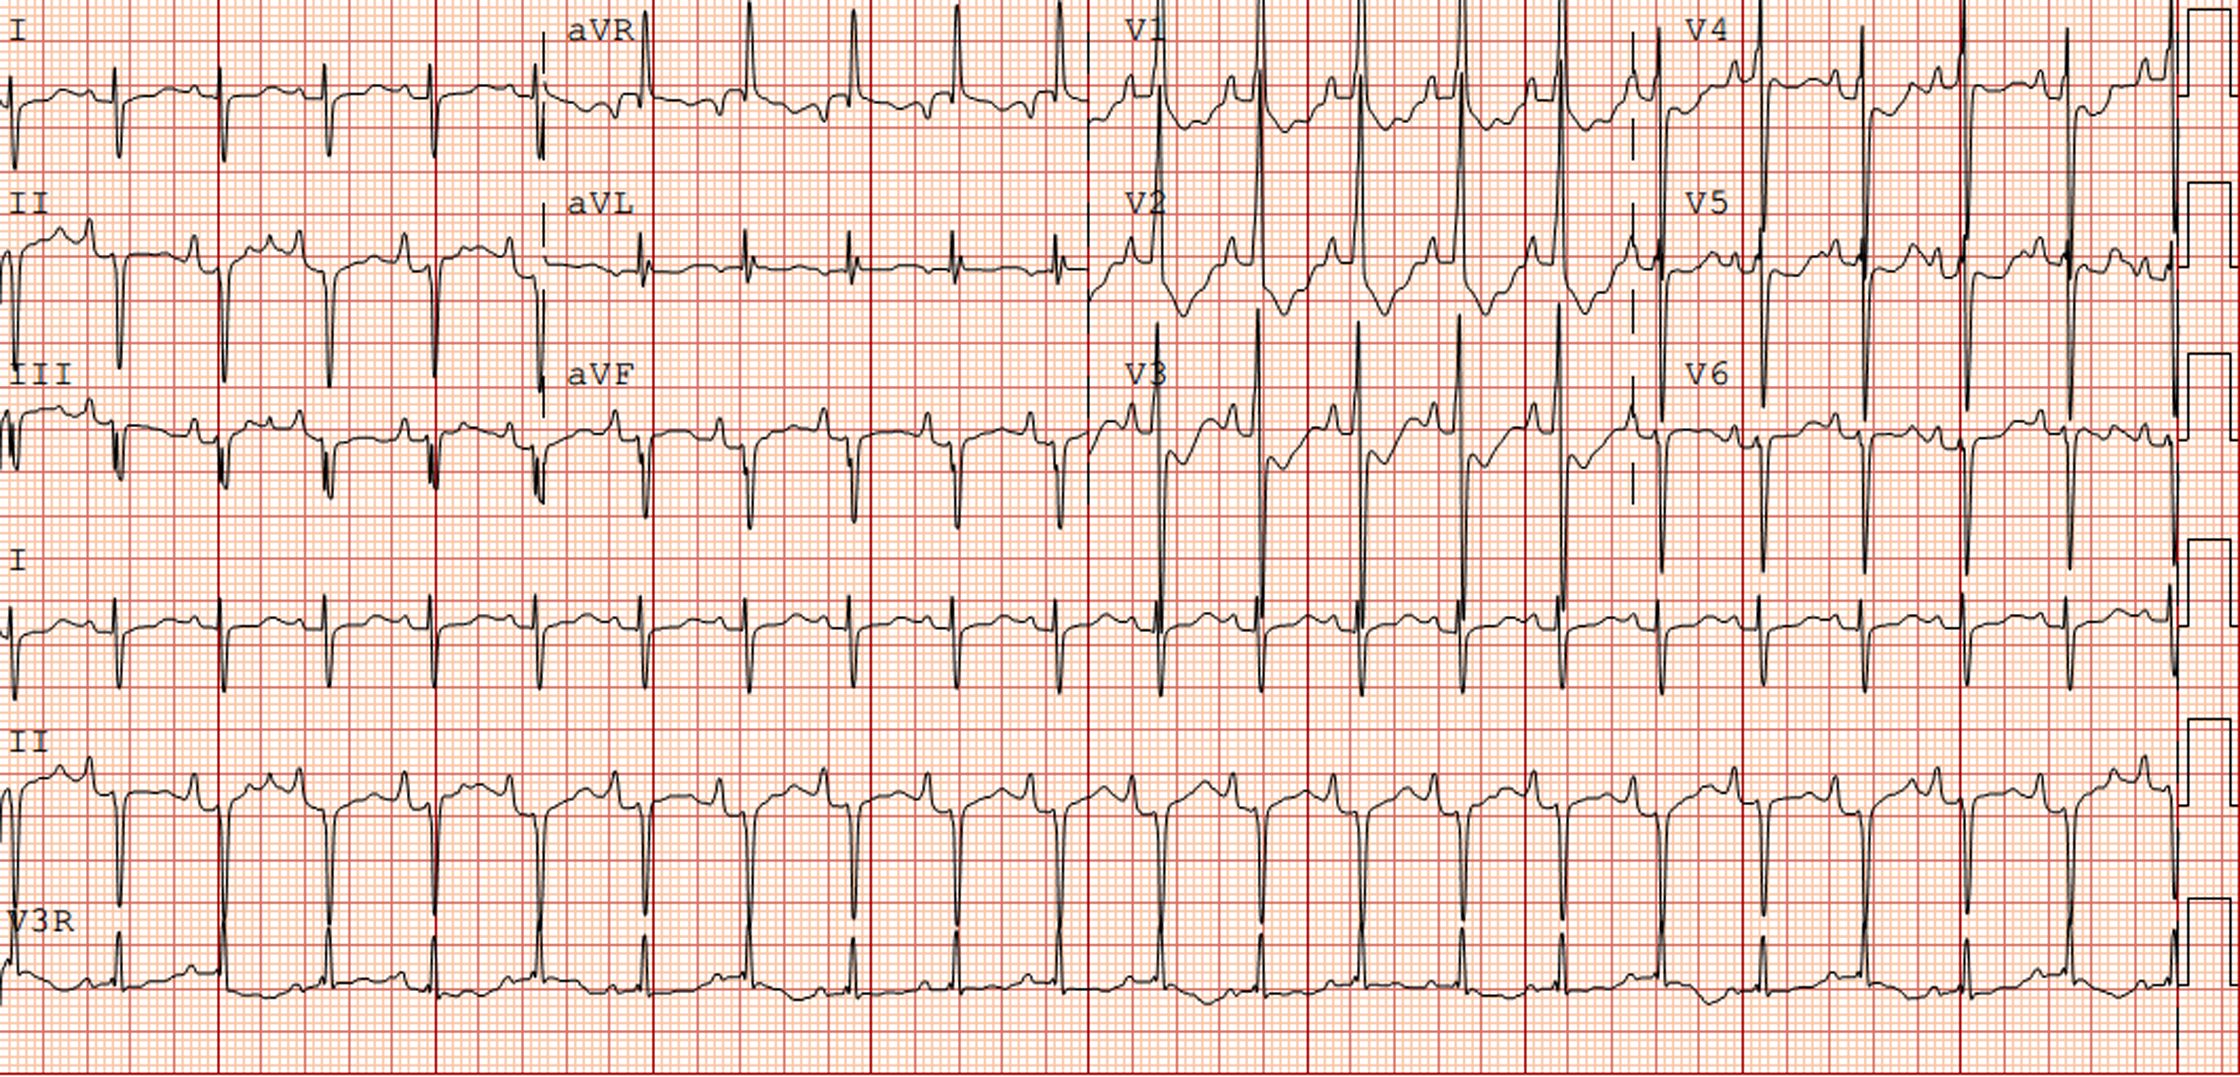

The electrocardiogram in patients with NS often shows typical features (Fig 1). These typical Noonan syndrome-related electrocardiographic features are left axis deviation, small R-waves in the left precordial leads, large S-waves in the right precordial leads, abnormal Q-waves, and/or wide QRS complex. Reference Croonen, van der Burgt, Kapusta and Draaisma7,Reference Raaijmakers, Noordam, Noonan, Croonen, van der Burgt and Draaisma13–Reference Bertola, Kim and Sugayama15 These typical electrocardiographic abnormalities are present in 50–60% of all patients with Noonan syndrome, and do not seem to be associated with the presence of a (specific) CHD and the presence of a PTPN11 mutation. Reference Croonen, van der Burgt, Kapusta and Draaisma7,Reference Raaijmakers, Noordam, Noonan, Croonen, van der Burgt and Draaisma13 The reason for these characteristic electrocardiographic features is still unknown. Reference Croonen, van der Burgt, Kapusta and Draaisma7,Reference Raaijmakers, Noordam, Noonan, Croonen, van der Burgt and Draaisma13,Reference Bertola, Kim and Sugayama15

Figure 1. Electrocardiogram (speed 25 mm/sec, voltage 0.1 mV/mm) from a newborn with Noonan syndrome due to PTPN11 mutation with a severe pulmonary valve stenosis.